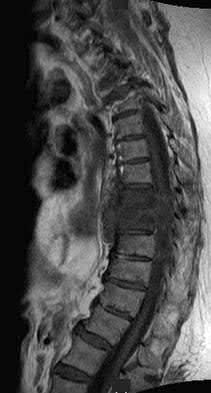

Figures 9a through 9c are the MRI scans of a 65-year-old woman on dialysis who has thoracic back pain, malaise, and an elevated erythrocyte sedimentation rate (ESR). The clinical history and imaging findings are most consistent with

Corrent answer: 3

The sagittal MRI scans are pathognomonic for diskitis and osteomyelitis with fluid signal and destructive changes in the disk on T2 (Figure 9a), low signal with blurring of the disk margins on T1 (Figure 9b), and on the T1 gadolinium image (Figure 9c) vertebral body enhancement on either side of the affected disk with dark signals within the disk corresponding to the bright fluid signal from the T2 image. Metastatic carcinoma tends to affect the vertebral body with relative disk sparing, and lymphoma can affect the vertebral body but often has soft tissue extending within the spinal canal. Osteoporotic fractures are contained with the vertebral body. Renal osteodystrophy can result in a diskitis picture with disk destruction but one would not expect an elevated ESR or malaise, and this is much rarer than diskitis in dialysis patients.